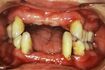

「40代は歯のメンテナンスの始めどきです。ケアを怠ると、50代でも歯が抜けてスッカスカになりますよ! おまけに全身疾患のリスクも高くなります」

厚生労働省の歯科疾患実態調査(H28年)によると、なんらかの理由で歯を失い「すべて自分の歯ではない」人の割合は、40~41歳で31・1%、45~49歳で41・1%と年を重ねるほどに増えていく。

50~54歳では61.5%と、なんと半数以上が歯を失っているというからシャレにならない。